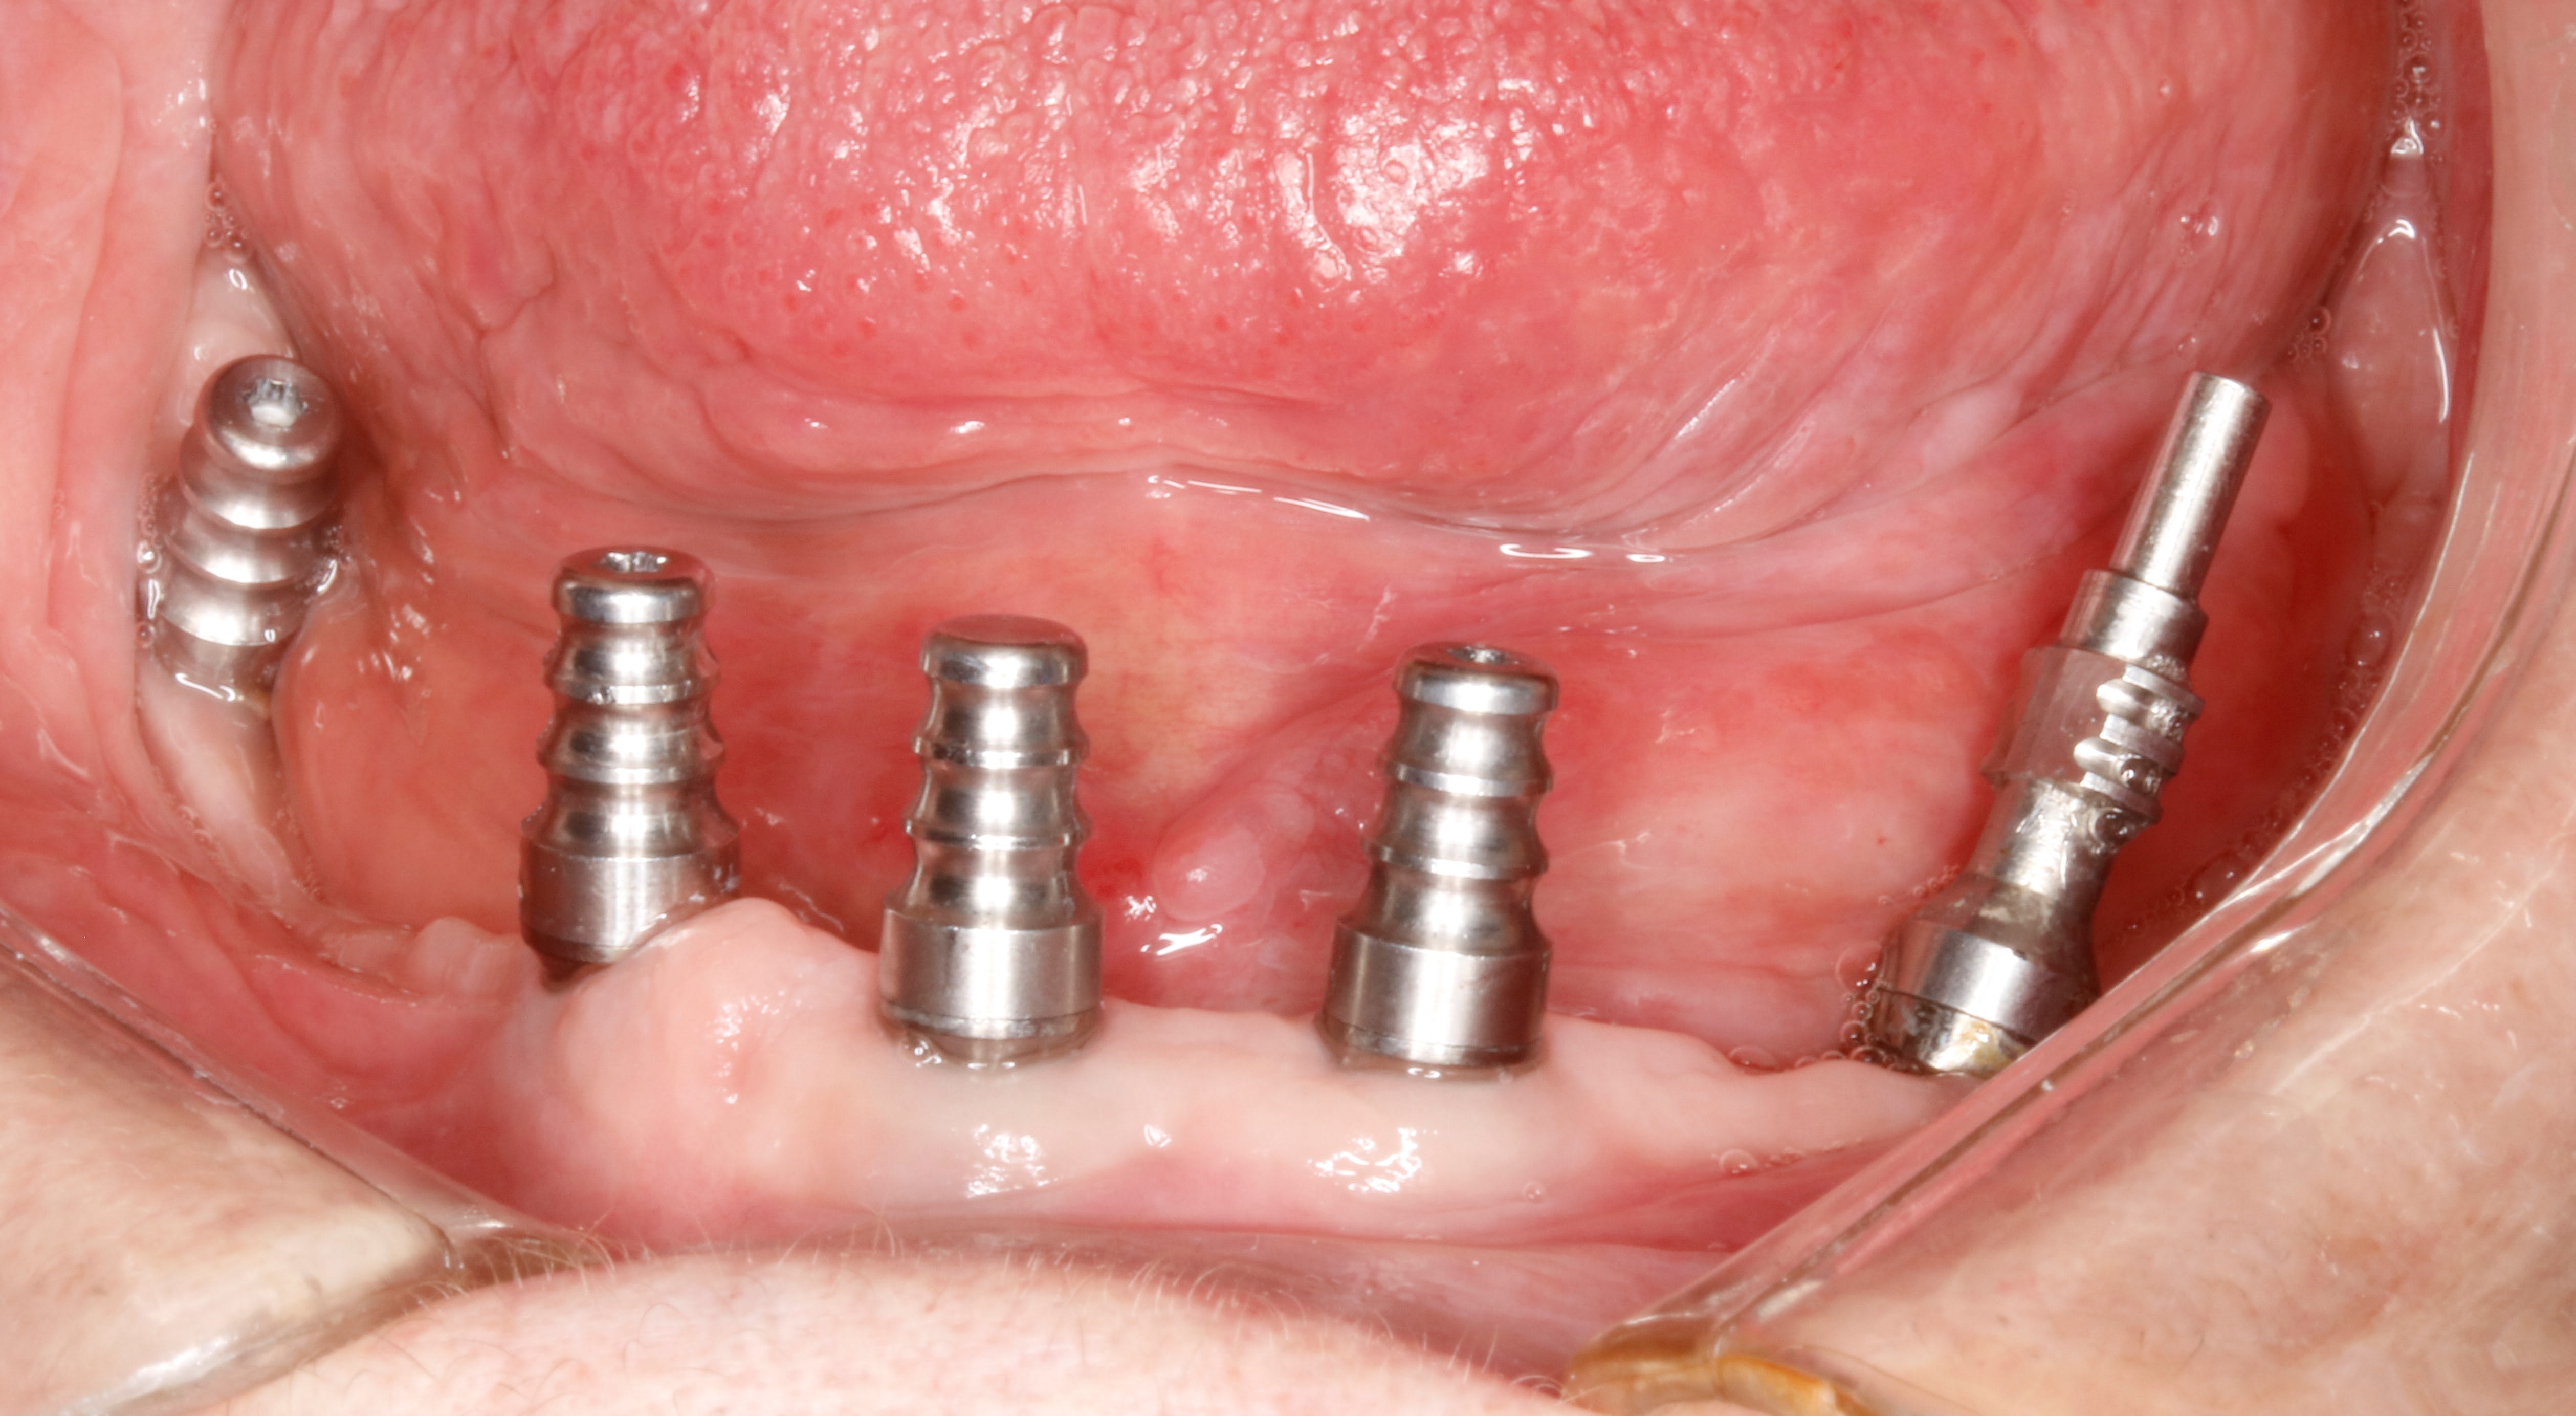

je dois faire une prothèse totale sur implant , je crois que c est ce que vous appelez pilotis .

et en position de 35&1/2 implant terminal , il y a un multi unit étrange qui compense l axe .

ce que je ne comprends pas , ç est l utilité de cet espace libre réceptacle de saloperies entre ce multi unit et l implant .

bon , c est bien beau tout ça mais maintenant je fais quoi ?

Tu peux essayer de diminuer au maximum le diamètre de ton pilier si ton système le permet...

Ou demander à ton prothésiste de lui même surtailler le pilier et lui demander de prendre pour limite le col de ton implant. C’est pas l’Amérique mais toute façon tu peux difficilement faire pire

Dernier truc, penses à polir la partie non enfouie de ton implant avant de poser, ça aidera aussi un peu